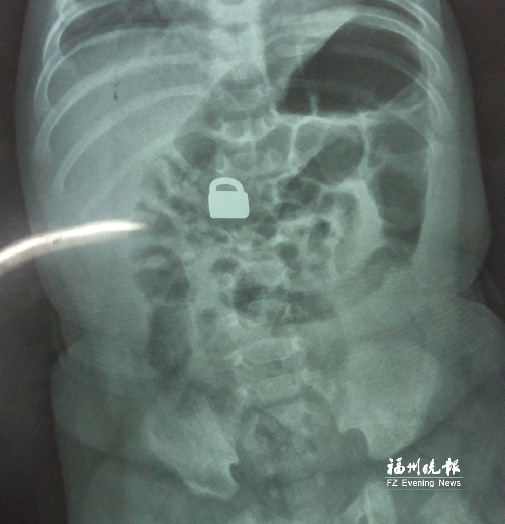

7.25龍巖當(dāng)?shù)蒯t(yī)院拍的X光片顯示,平安鎖在寶寶體內(nèi)。

這名60天大的“神奇寶寶”來(lái)自龍巖,哥哥也只有兩歲。7月25日,兄弟倆的媽媽突然發(fā)現(xiàn)寶寶胸前掛著的平安鎖不見(jiàn)了,便問(wèn)小哥哥是否看到弟弟的平安鎖。小哥哥回答,他把平安鎖塞到弟弟嘴里了。媽媽趕緊檢查寶寶嘴巴,沒(méi)有發(fā)現(xiàn)平安鎖。雖然寶寶沒(méi)有任何癥狀,但媽媽還是帶著他去當(dāng)?shù)蒯t(yī)院檢查。拍片結(jié)果顯示,平安鎖真的在寶寶體內(nèi)。

“X光片顯示,那是一把1.5厘米×0.9厘米的平安鎖,有指甲蓋大小,已經(jīng)到了寶寶的小腸處?!?月28日,陳惠萍見(jiàn)到寶寶時(shí),吃了一驚,“他真的好小,被抱在媽媽?xiě)牙?,眼睛微微睜開(kāi),我估計(jì)他的世界還是混沌的,沒(méi)想到就已經(jīng)接受了這么大的挑戰(zhàn)?!?/p>